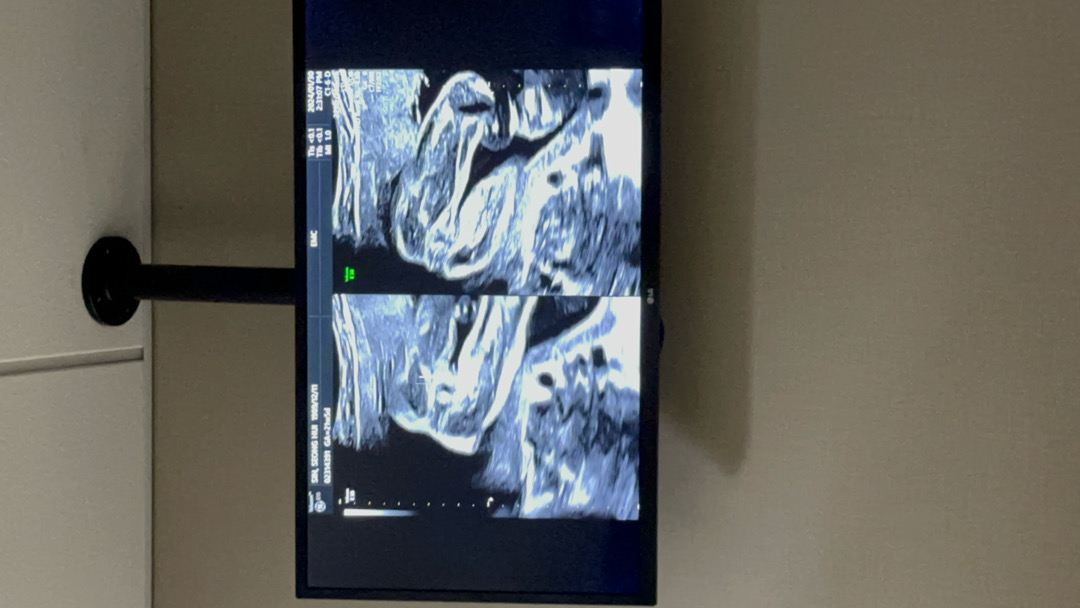

21주 오늘 촘파 사진이예용!

오늘 정밀촘파 사진이예용 ㅎㅎ 제 눈엔 정말 안 보이는데 맘님들 눈에도 같은가요? 🌶️🌶️🌶️🌶️없는거죵 ㅠㅠ?

21주차에 남자아이였음 존재감 쁌뿜이라고 했어요~~~ 곤쥬님인거같아용~~

제눈에두 없어보여용~.~